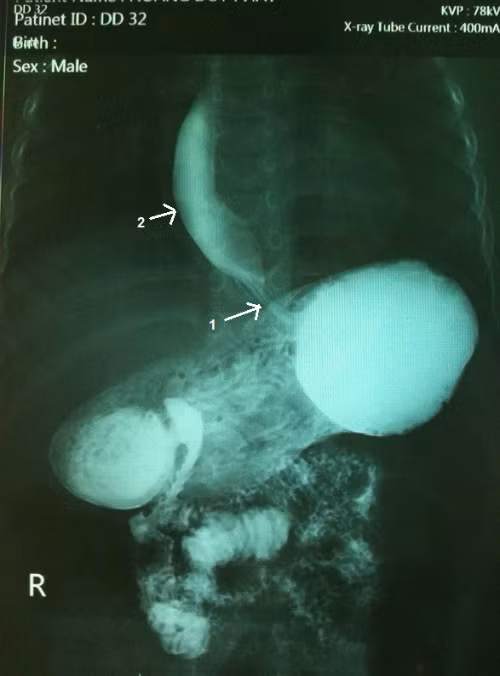

Ảnh chụp Xquang của cháu Duy cho thấy đoạn cuối của thực quản nơi đổ vào dạ dày bị co thắt và hẹp lại, đoạn trên bị giãn to ra. Ảnh: Khánh Chi.

Đoạn cuối của thực quản nơi đổ vào dạ dày bị co thắt và hẹp lại, còn đoạn trên bị giãn to ra. Nếu không được phát hiện và điều trị kịp thời có thể dẫn tới các biến chứng như: viêm loét thực quản, sẹo xơ gây chít hẹp thực quản thậm chí tử vong đột ngột do phản xạ tim mạch hay dây thần kinh 10, do ngạt thở vì trào ngược thức ăn vào khí quản, hay do suy dinh dưỡng ở giai đoạn muộn.